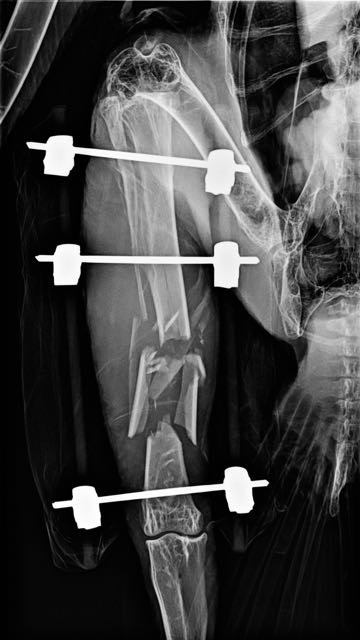

Bald Eagle 18-016 Update

Dr. Katie Yackley, Pendleton Veterinary Clinic, repaired the broken leg of the adult Bald Eagle from Enterprise. She placed three pins perpendicular to the long axis of the bone, two above the fracture and one below the fracture. The pins are connected by rods (that don’t show on the radiograph) on either side of the leg. This method of stabilization allows traction to be used to align the multiple pieces of broken bone.

The eagle is able to stand briefly, using his broken leg to balance, but is spending most of his time lying down. The surgery didn't affect his appetite. He has been eating voraciously.